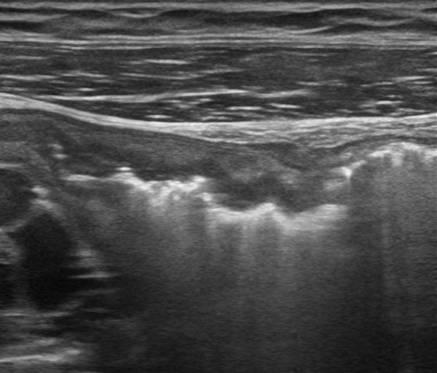

Viêm ruột

» Thông tin: Nữ giới – 18 tuổi.

» Lâm sàng: Tiêu chảy.